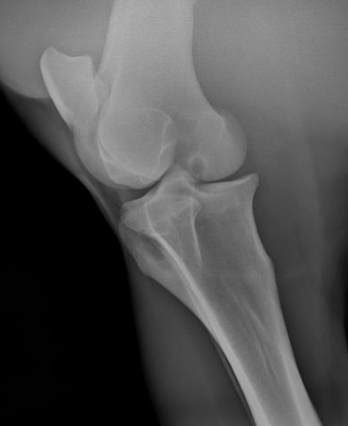

39

osteochondrosis is common in

young growing large breed dogs and horses

40

what disease process is this?

osteochondrosis